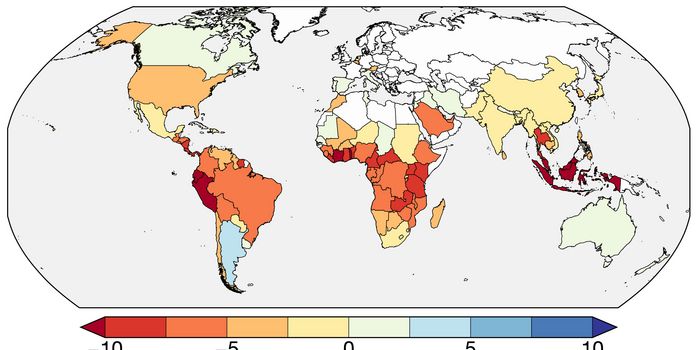

MAY 17, 2024Earth & The EnvironmentScientists are trying to learn more about the exact factors that promote the spread of disease, in part because that wil ...